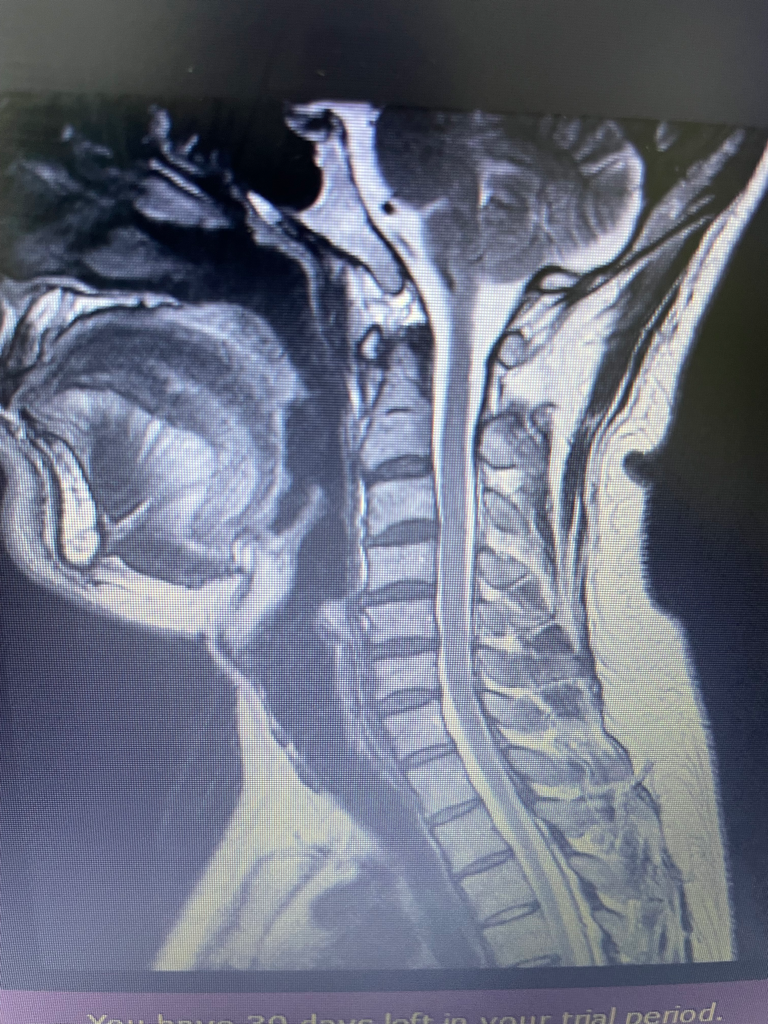

목디스크 신정운동 한의원치료 신경와과치료

목디스크

목디스크 4말 목어깨통증 5월초 팔통증 6월7일 시술

아직도 목뻐근 고개 무서워서 돌리지 못함 mri목디스크 많이 심함가요 6개월쯤 되었는데 언제쯤 나을까요 그리고 목 신전운동 하고 있는데 더 뻐근한데 이거 해야 하는 건가요? 고개는 돌려도 될까요 솔직히 이정도도 많이 나아 진건데 다시 통증이 또 올까봐 무섭습미다 .